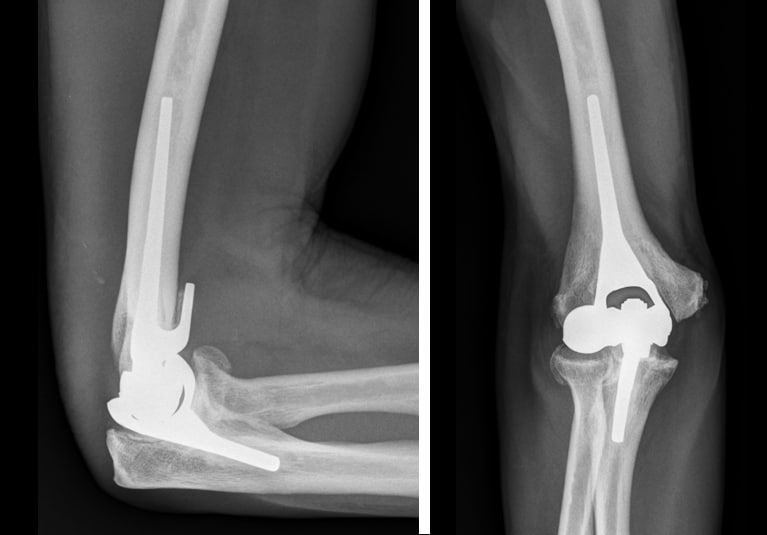

Total elbow replacement: Matching the success of hips and knees

Mayo Clinic has pioneered an approach to elbow replacement surgery that seems capable of offering young, active patients a stable and durable treatment. A 20-year effort initiated by Mayo Clinic has resulted in the development of a prosthetic elbow and surgical technique that appear to provide an elbow replacement with quality approaching that of hip and knee replacements.

Dr. O'Driscoll and colleagues at Mayo Clinic and other centers have been implanting the elbow design since 2001. "With a follow-up of up to 16 years, rates of revision due to wear are truly minimal," he says. "We will continue to study the procedure's longevity, but I think we can say we are accomplishing our goal of bringing elbow replacement to the level of hip and knee replacement."

The researchers have also sought to solve problems with elbow prosthetics' stability and durability. "The new design has a much thicker polyethylene lining and a much broader surface area, so the pressures placed on the joint are distributed much more evenly," Dr. O'Driscoll says.

"The design was accomplished with computer optimization so that at any particular position throughout the entire range of motion — or during angular deflections when the joint is trying to be torqued out of place — the surface area never diminishes to an area small enough to concentrate pressure and wear out the plastic."